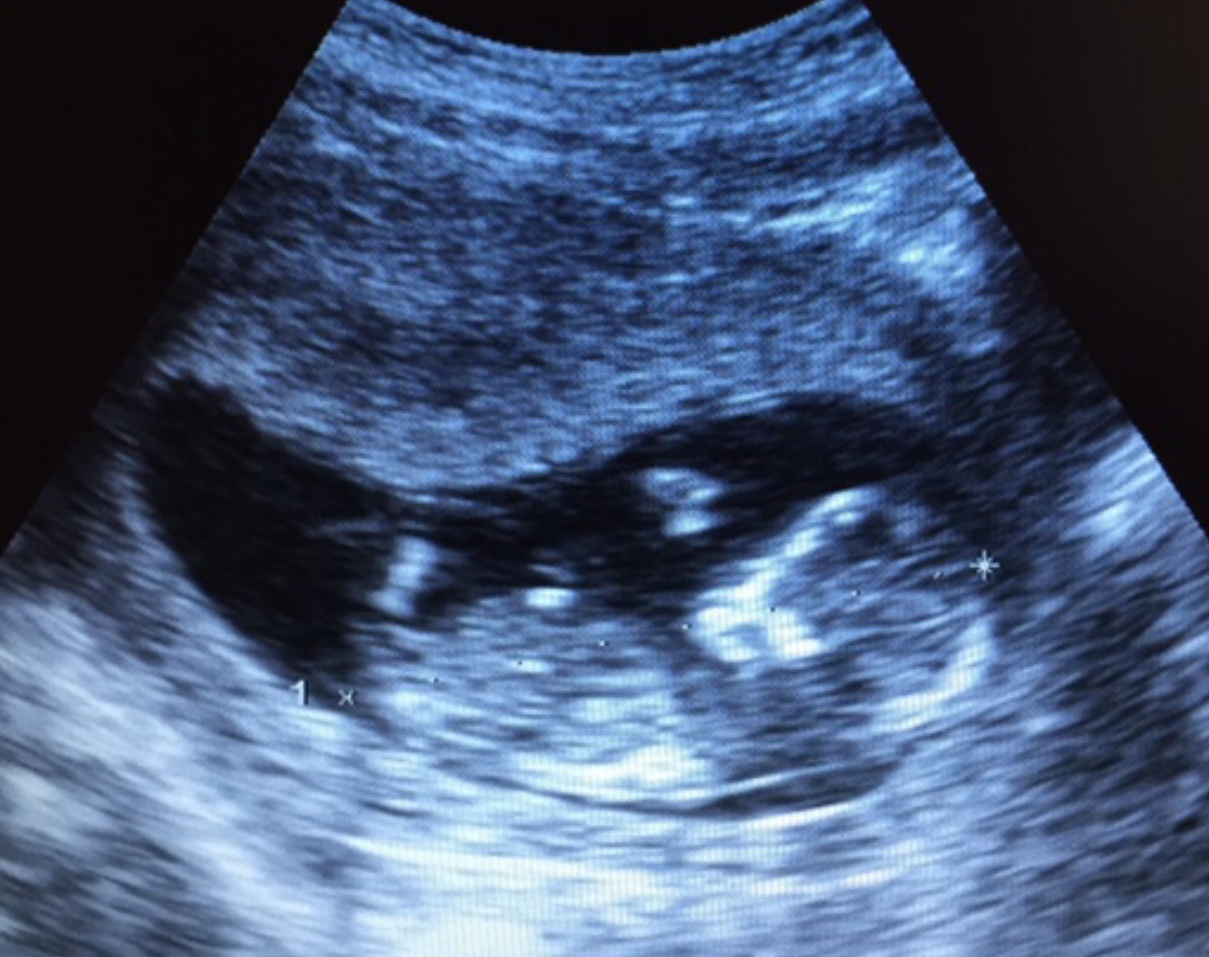

Tambien se incluye el estudio del embarazo normal y todas sus patologias hasta el puerperio.